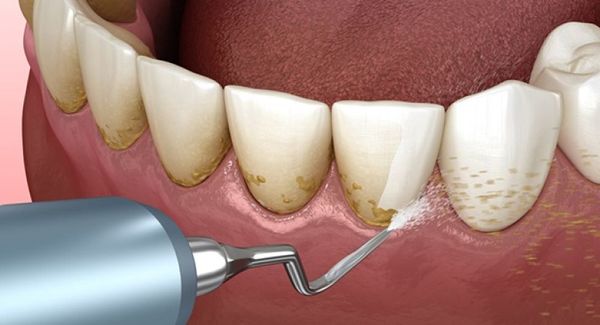

Cao răng tạo thêm diện tích cho mảng bám phát triển, gây ra các bệnh nghiêm trọng như sâu răng và bệnh nướu. Vôi răng không thể tự loại bỏ bằng bàn chải hay bất kỳ dụng cụ nào khác. Việc làm sạch cao răng cần được thực hiện tại phòng khám nha khoa bởi nha sĩ, sử dụng kỹ thuật và máy móc chuyên dụng. Quá trình này gọi là lấy cao răng, thường kết hợp với đánh bóng răng.

cạo vôi 2 Cạo vôi răng giúp hàm răng của bạn trắng sáng hơn

Cạo vôi là phương pháp loại bỏ mảng bám bẩn ở răng ,nhưng cũng không vì thế mà chúng ta lạm dụng quá,nên định kỳ 3-6 tháng lấy một lần ngoài ra còn phụ thuộc vào sức khỏe của răng và độ bám hình thành nên mảng bám mà bác sĩ có chỉ định riêng biệt:

Trên thực tế, cạo vôi răng là thủ thuật nha khoa giúp lấy sạch những mảng bám bị vôi hóa trên răng và nướu giúp răng miệng trở nên sạch sẽ và ngăn ngừa các bệnh lý nha khoa nghiêm trọng.

Tuy nhiên, chúng ta không nên lạm dụng việc cạo vôi răng vì điều này sẽ gây tổn thưởng răng của bạn. Hãy cạo vôi răng định kỳ 6 tháng/lần hoặc theo chỉ dẫn của nha sĩ để đạt được hiệu quả tốt nhất.